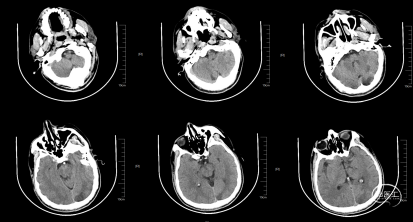

头CT(急诊):左侧小脑半球、左侧放射冠、半卵圆中心、额顶枕叶脑梗死。

术前CT,ASPECT 8分。